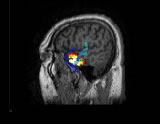

多模式神經(腦)影像、腦活動源精確定位、2D/3D影像,CURRY是功能非常強大的電磁溯源分析定位和可視化工具,該軟件在世界上處于最領先地位,推動了神經(腦)影像的飛速發展。

CURRY軟件包含多種功能,可以充分整合各種影像數據格式(EEG、MEG、MRI、fMRI、CT等)。通過將腦電活動與各種自發或功能影像數據的有機融合,CURRY為腦活動源的定位和分析提供了強有力的工具。CURRY可以利用MR和CT等得到的真實解剖結構影像,建立每個被試的顱骨和腦的3D模型(該模型對探明神經活動的發生源至關重要)。CURRY還可以將功能影像(如fMRI)和EEG、MEG的溯源重建進行比較,以增強結果的準確性。 CURRY可以在PC機、工作站、Laptops等運行,不僅可以用于研究工作(如腦的功能成像),而且,其強大的功能和先進性使其具有了更為廣泛的應用(如臨床、功能評估等)。

CURRY最強大的功能之一是其能夠重建每個被試的真實頭模型(Realistic head model)。該過程是非常精確并高度自動化的。首先,讀取MRI的每個斷層影像,生成等方形的3D MRI數據組;然后用該數據組識別并重建諸如皮層、顱骨、頭皮或皮層斷層的3D結構,用來構筑一個BEM模型(Boundary Element Model)。如果沒有解剖結構數據,CURRY也可以用簡單的多球頭模型進行皮層、顱骨或頭皮的3D重構。

CURRY可以清晰地呈現具有高分辨率的各種影像及3D 重建結果(皮層、顱骨、頭皮、皮層斷層)。同時,可以觀察3D影像結果的動態變化(如3D Movie),具有很高的時間分辨率,也可以進行體積測量。